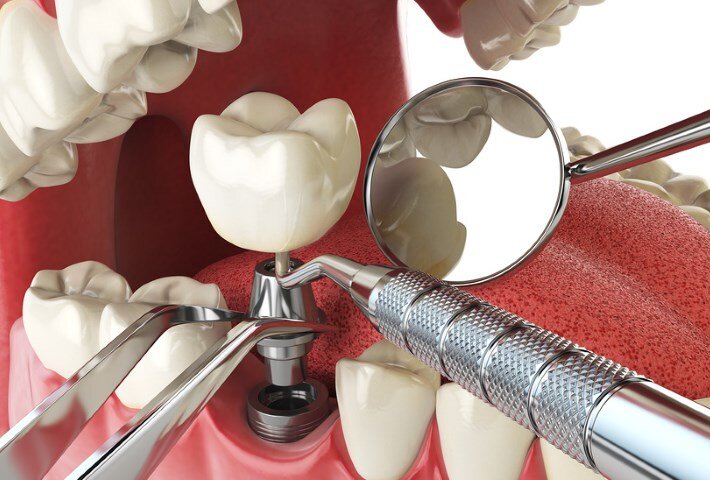

Имплантация зубов - это довольно молодой метод восстановления зубов, первый эксперимент по установке имплантата был проведён в 1965 году, однако, массовое распространение они получили лишь в начале 80-х годов, и раньше процент отторжений был довольно высокий. Однако, сегодня имплантация стала, пожалуй, лучшим методом для восстановления функциональности зубов с успешностью более 98%.

• Пройти консультацию. Как любое важное дело, имплантация начинается с планирования. Первичный осмотр у врача-имплантолога, на которой доктор знакомится с ситуацией и предлагает варианты решений, опираясь на опыт. Изучение компьютерной томографии (КТ), на которой видно буквально всё. Эти первые шаги помогут точно знать, что нужно сделать и сколько это будет стоить.